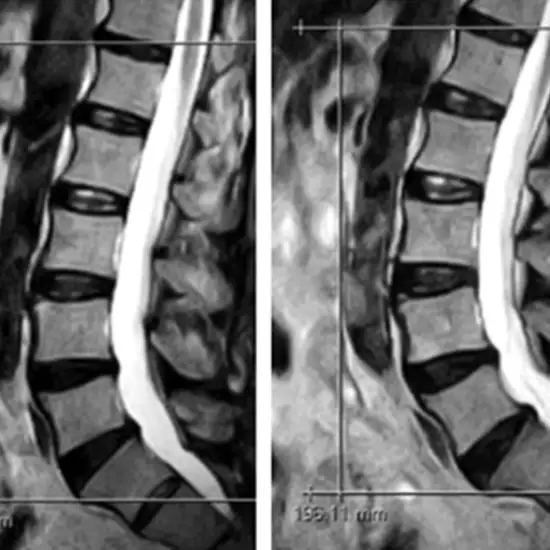

MRI LS Spine Axial Cuts (magnetic resonance imaging lumbosacral spine axial cuts) is an imaging procedure showing the measurement of the anteroposterior diameter of the spinal canal at the disc level. It is recommended in a case of intervertebral disc herniation without cauda equina syndrome.

• Provide optimal view to Visualize the disk herniations

• Suspected spinal stenosis